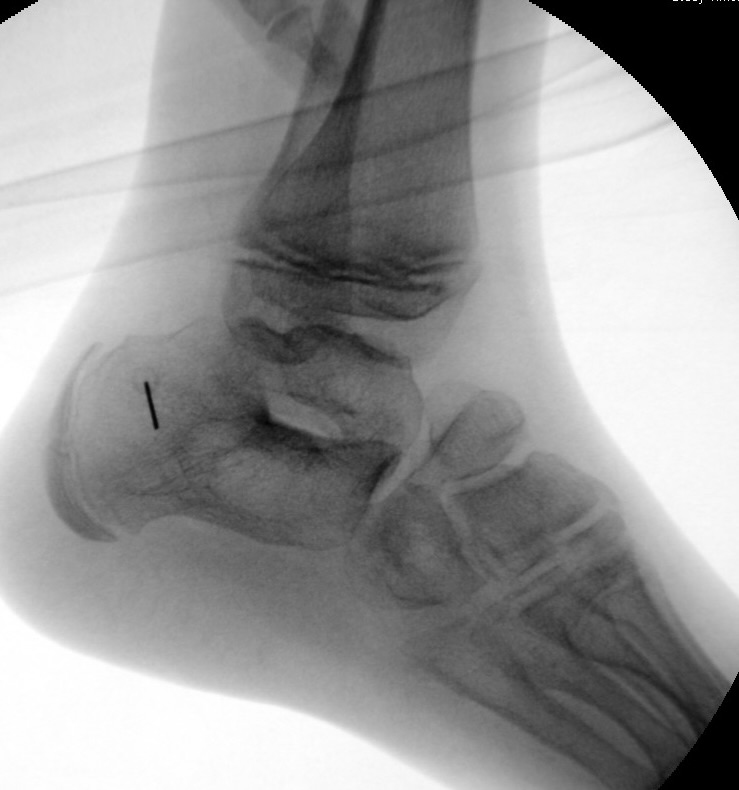

Diagnostisches Vorgehen

Damit die minimalinvasive Fußchirurgie zur Korrektur kindlicher oder jugendlicher Fußdeformitäten erfolgreich angewendet werden kann, erfordert die präoperative Diagnostik Röntgenbilder in drei Ebenen am stehenden Fuß. Röntgenbilder ohne Belastung des Fußes sind nicht zielführend. Im Fall von schweren Rückfußdeformitäten wird das obere Sprunggelenk in die radiologische Diagnostik mit einbezogen in Kombination mit der Rückfußaufnahme unter Belastung („Saltzman View“). Das OSG wird in zwei Ebenen geröntgt. Die streng seitliche Aufnahme des OSG kann bei den komplexen Fußdeformitäten mit der seitlichen Aufnahme des Fußes unter Belastung kombiniert werden. Das reduziert die diagnostische Strahlenbelastung der Kinder.

Indikationen für die beschriebenen Röntgenaufnahmen sind Klumpfußdeformitäten zur Beurteilung eines „flat top talus“ oder neurologische Grunderkrankungen mit varischer Fersenstellung wie zum Beispiel bei HSMN (Hereditäre Sensorische Motorische Neuropathie).